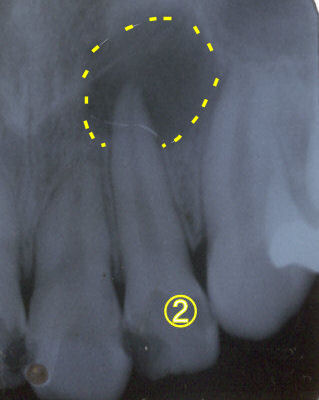

歯の根の治療

何度か腫れを繰り返した歯(7番)でした(写真1)。歯の根の治療は先の方まで薬が入っています。歯周ポケットは4mm程度で根の先まで交通していませんでした。根の先から亀裂が入っていると診断して矯正力をかけた後に一旦抜歯しました。やはり根の先に亀裂が入っていました。その部分のみを切断、逆根充して(写真2)再び抜歯窩にもどして固定しました。2ヶ月後に最終の冠を入れました(写真3)。動揺もなくしっかり噛めるようになったそうです。根の先の病変の影も薄くなっています(写真4)。 |